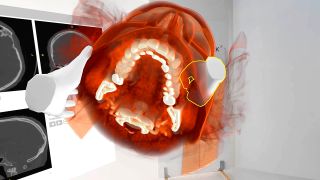

Intraoperative holographic navigation with augmented reality in mandibular reconstruction Publication

Intraoperative holographic navigation with augmented reality in mandibular reconstruction

Reconstructing large mandibular defects remains one of the most demanding procedures in head and neck surgery. Tumor-related bone destruction affects chewing, facial symmetry, speech, and patient quality of life.